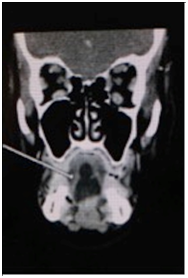

A 57-year-old Caucasian female was flown from a remote location to the emergency department for emergent consultation for a possible sublingual abscess. She complained of increasing right jaw pain and difficulty opening her jaw. The patient was afebrile and non-toxic appearing. Physical examination revealed right temporomandibular joint pain upon palpation, trismus, and slight fullness of the oral tongue and floor of the mouth. Initial laboratory data was within normal limits and was not significant for an acute inflammatory process. Computed tomography with intravenous contrast was performed and revealed a 2x3 centimeter intralingual hypodense fluid collection possibly representing an abscess (Figure 1). A trans-oral needle aspiration was performed to determine the nature of the cystic lesion. Approximately three cubic centimeters of yellow, thick, cheesy material was aspirated and sent for cytology. The patient was then discharged with a presumed diagnosis of dermoid cyst, dietary modifications for her temporomandibular joint syndrome, prophylactic oral clindamycin, and recommendation to return for surgical excision of the cyst. One week later, the patient returned to the emergency department complaining of increased swelling of the oral tongue and floor of mouth. The patient once again remained afebrile and non-toxic appearing. A repeat trans-oral needle aspiration revealed purulence and the patient was subsequently admitted to the hospital for intravenous ampicillin/sulbactam and scheduled for excision of the cyst at the next available operating time.

Figure 1(a-c) Pre-operative CT images with intravenous contrast demonstrating the intralingual fluid collection consistent with presumed abscess but post-operatively confirmed by pathology as a dermoid cyst.